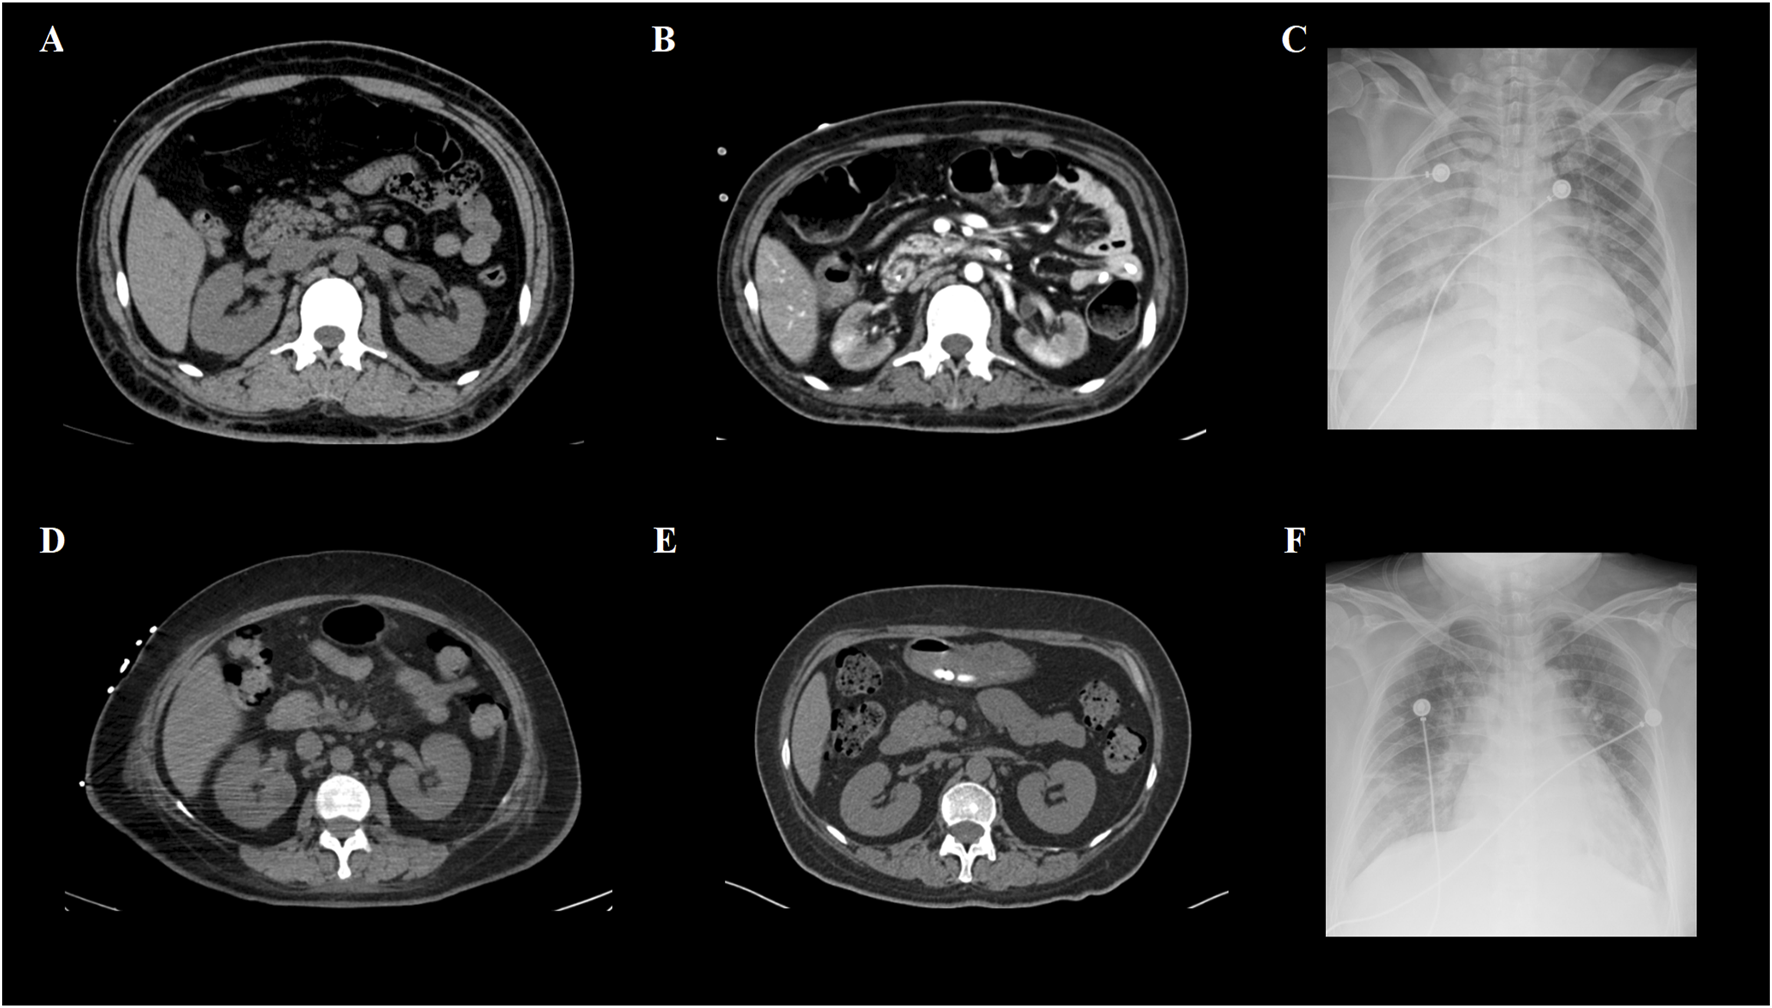

A total of 8/26 (30.8%) patients received CRRT due to the development of anuria and/or congestive heart failure. The clinical characteristics of these eight patients are summarized in Table 2. Among them, three were high-risk APL patients, and two had extreme hyperleukocytosis, defined as an initial WBC count exceeding 100 × 109/L. Seven patients experienced rapid and remarkable WBC elevation as a sign of DS. AKI generally develops within 5 days (range, 0–5 days) after induction. Five patients survived for more than 3 months. Nevertheless, three of these five non-ED patients were still dependent on regular hemodialysis without renal function recovery during the follow-up. Among the eight patients who received CRRT, two patients (patients #2 and #5) underwent abdominal computerized tomography (CT) when AKI occurred, and bilateral kidney swelling and slight nephromegaly were found on CT imaging in both patients (Figures 1A, D). In addition, both patients developed pulmonary edema and infiltration on chest X-ray, which indicated severe DS (Figures 1C, F). Moreover, obvious decreases in renal size and hypoperfusion signs were observed on serial CT 3 months later in patient #2, who experienced persistent renal dysfunction and was continuously dependent on dialysis. In contrast, patient #5 had restored normal renal function, and CT imaging 2 months later revealed the disappearance of renal edema with the restoration of the normal kidney size (Figures 1B, E). One patient (patient #2) had simultaneous monitoring of interleukin (IL)-6 and C-reactive protein (CRP) levels during the development of DS. A synchronized change in the WBC and cytokine trends was documented (Figure 2). Among the 18 patients who had AKI but did not require renal replacement therapy in the induction phase, 11/18 (61.1%) patients were demonstrated to have normalized renal function and survived over 3 months of follow-up. Nevertheless, the remaining 7/18 (38.9%) patients either developed chronic kidney disease or experienced ED.

FIGURE 1

CT and X-ray images of two APL patients with renal failure. (A) Abdominal CT of patient #2 revealed kidney swelling and enlargement when DS occurred. (B) Patient #2 had persistent renal dysfunction and became dialysis-dependent after achieving complete remission of APL. Enhanced CT imaging 3 months later revealed kidney shrinkage and decreased contrast intake at focal sites, which was consistent with irreversible changes in the renal function. (C) Obvious bilateral pulmonary infiltrates caused by DS were demonstrated by the chest X-ray of patient #2. (D) Abdominal CT of patient #5 also revealed kidney swelling and enlargement in the DS. (E) Unlike patient #2, the renal function of patient #5 was restored to normal after DS was successfully managed. Non-contrast CT imaging 2 months later revealed that both kidneys had normal appearances. (F) Similar to patient #2, patient #5 developed pulmonary infiltration, shown as patch opacities on the chest X-ray at the pinnacle of the DS.

The etiopathogenic mechanisms of DS as a life-threatening complication in APL patients are complex and remain incompletely understood. Moreover, the exact mechanism behind this irreversibility of renal dysfunction is not well-understood. The hypothesis is that DS behaves like a systemic inflammatory response system and capillary leak syndrome (Iyer et al., 2023). ATRA targets the ATRA receptor and induces terminal differentiation of APL blasts. The differentiation of APL cells can stimulate chemokine production in target organs. These chemokines serve as chemoattractants for other inflammatory cells, which further exacerbates the hyperinflammatory state (Luesink et al., 2009b). Thus, AKI in APL patients could result from a therapeutic intervention-induced cytokine storm syndrome (CSS), similar to the hyperinflammation status following immunotherapy, such as monoclonal antibody administration and chimeric antigen receptor (CAR) T-cell therapy (Karki and Kanneganti, 2021). CSS is triggered by the activation of bystander cells, particularly myeloid cells, in the tumor environment. Subsequent inflammatory cell death and tumor lysis induce CSS through the release of inflammatory cytokines (Lee et al., 2014). Pro-inflammatory cytokines, including IL-6, IL-1, and IFN-γ, are consistently elevated in the serum of patients with CSS (Liu et al., 2020). Another contributing factor is coagulopathy, which is extremely common in cytokine storm-related conditions. In addition to DIC, coagulopathy in CSS is a thrombotic or hypercoagulable condition due to the interplay between inflammation and clotting cascades. Like in COVID-19 infection, the systemic inflammatory state can trigger coagulation cascades, which, in turn, activate the production and release of pro-inflammatory mediators via positive feedback mechanisms (Savla et al., 2021). In the setting of DS, leukostasis secondary to hyperleukocytosis could further aggravate microthrombosis and tissue ischemia of the target organ. The rapid correction of the hypocoagulable status after induction therapy in APL patients makes microthrombosis more troublesome in capillary-rich organs such as the kidney. Moreover, lower oxygen delivery to the kidney, directly or indirectly caused by interstitial edema, vasoconstriction, circulation collapse, respiratory failure, and septic complications, could also contribute to the development of AKI (Ahmadian et al., 2021). Thus, if the cytokine storm cannot be harnessed in time, inflammation-related tissue injury and cellular necrosis rapidly develop widespread microthrombosis, and hypoperfusion might work together to explain permanent kidney injury. Unfortunately, owing to the obvious coagulopathy and critical condition of APL patients during the induction period, renal biopsy is almost impossible. However, some postmortem studies of patients with DS-related renal failure have shown diffuse neutrophilic and leukemic infiltration in multiple organs, including the kidney (Flombaum et al., 1996; Kakkar et al., 2002). The infiltration of leukemic cells is suggested to be mediated by the release of a variety of cytokines by differentiating blast cells and the altered adhesion properties of the blast cells after being primed by ATRA (Woods and Norsworthy, 2023). ATRA treatment can increase the expression of adhesion molecules such as CD11b, CD18, and ICAM-1, which increases the adhesion of myeloid cells to endothelial cells, facilitating their migration into tissues (Mohammadzadeh et al., 2021). The presence of enlarged kidneys shown by ultrasonography during the period of leukocytosis, the disappearance of nephromegaly after recovery, and the prompt response to steroids and chemotherapy in previous reports were highly suggestive of leukemic infiltration of the kidneys under the inflammatory storm as the cause of renal failure (Montesinos and Sanz, 2011; Frankel et al., 1992). The morphological changes in the kidneys observed via serial CT imaging in our study also reflected this pathophysiological process. Moreover, in our study, two of the five non-ED patients did not receive dialysis, and the peak WBC counts of the two survivors were 7.69 and 19.8 × 109/L, respectively, which were much lower than those of patients who had ED- or dialysis-dependent survival. Thus, when DS occurs, the rate at which the WBC count increases and the peak WBC count during the differentiation process could be associated with the severity of leukemic infiltration in affected organs and with unfavorable outcomes in APL patients. Thus, AKI in DS patients is considered a multifactorial event.